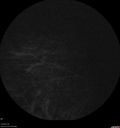

88 year old female with melanosis oculi and 2.5 mm elevated choroidal melanoma. She also has AMD with geographic atrophy. The right eye is the better eye. The left eye had a macular hemorrhage from wet AMD and breakthrough vitreous hemorrhage.